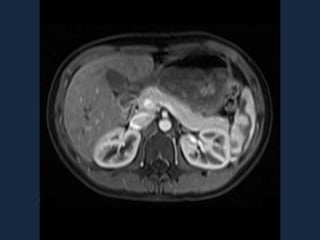

Ecografía endoscópica

Detecta el 77% de los insulinomas en el páncreas su rendimiento es mayor en

combinación con la TC. Tenga en cuenta lo siguiente:

1.- En tiempo real la Ecografía transabdominal de alta resolución tiene una sensibilidad

del 50%.

2.- La Ecografía Intraoperatoria Transabdominal de alta resolución detecta más de 90% de

los insulinomas.

Realización de un estudio preoperatorio para localizar el tumor seguida de la ecografía

intraoperatoria y un examen físico no es irrazonable.

a) la apariencia típica de la USE insulinoma: una masa de 1,5 mm

hipoecoica bien definido en la mitad del cuerpo del páncreas. (B) Dos

insulinomas muy pequeñas (flechas) que mide menos de 5 mm en el

páncreas distal.